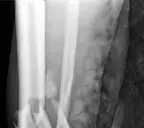

Distal Tibia Medial plating and screws Case description A 65-year-old man fell down a flight of stairs and pr…